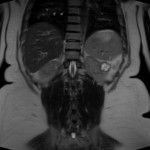

[IRM] Reins